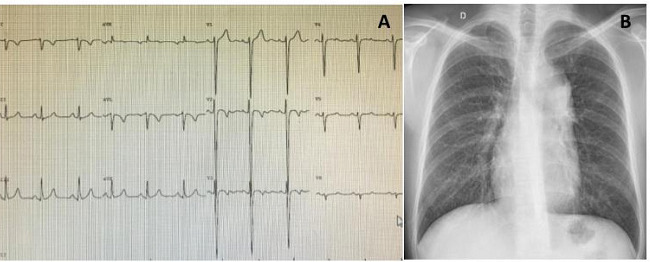

Medical treatment: Patients with isolated CCTGA, having associated lesions of minimal or no clinical significance, may enjoy an almost normal life as long as RV function is preserved. Reports of older patients having normally functioning RV provide evidence that, in some cases, the RV is able to adapt remarkably well to systemic pressure[28]. Predicting who will develop heart failure secondary to RV dysfunction is difficult, but symptoms usually start after the 4th decade of life, sometimes with associated LV dysfunction[12] (Figure 4). Why some patients develop RV dysfunction early in life and others do not is not entirely clear and is, likely, multifactorial. Patients with CCTGA that have a single RCA supplying the morphological, hypertrophied RV are at risk for RV ischemia, which may be complicated and/or exacerbated by coronary artery disease[21]. An experimental model of RV hypertrophy induced by PA banding in rats six hours after birth was created[29]. Different of another model in which young larger animals were used[30], this recently reported project aimed to study the pathophysiological changes in CHD with increased afterload which could, eventually, be applied to patients. For medical treatment, reduction of afterload with angiotensin-converting enzyme inhibitors or angiotensin II receptors might help patients with RV dysfunction despite limited data available. Though there have not been any studies to guide clinicians, the empiric use of diuretics, including aldosterone antagonists, essential for symptomatic patients with LV failure, are commonly used in patients with systemic RV failure. Beta blockers should be used with caution due to the propensity for heart block[14].